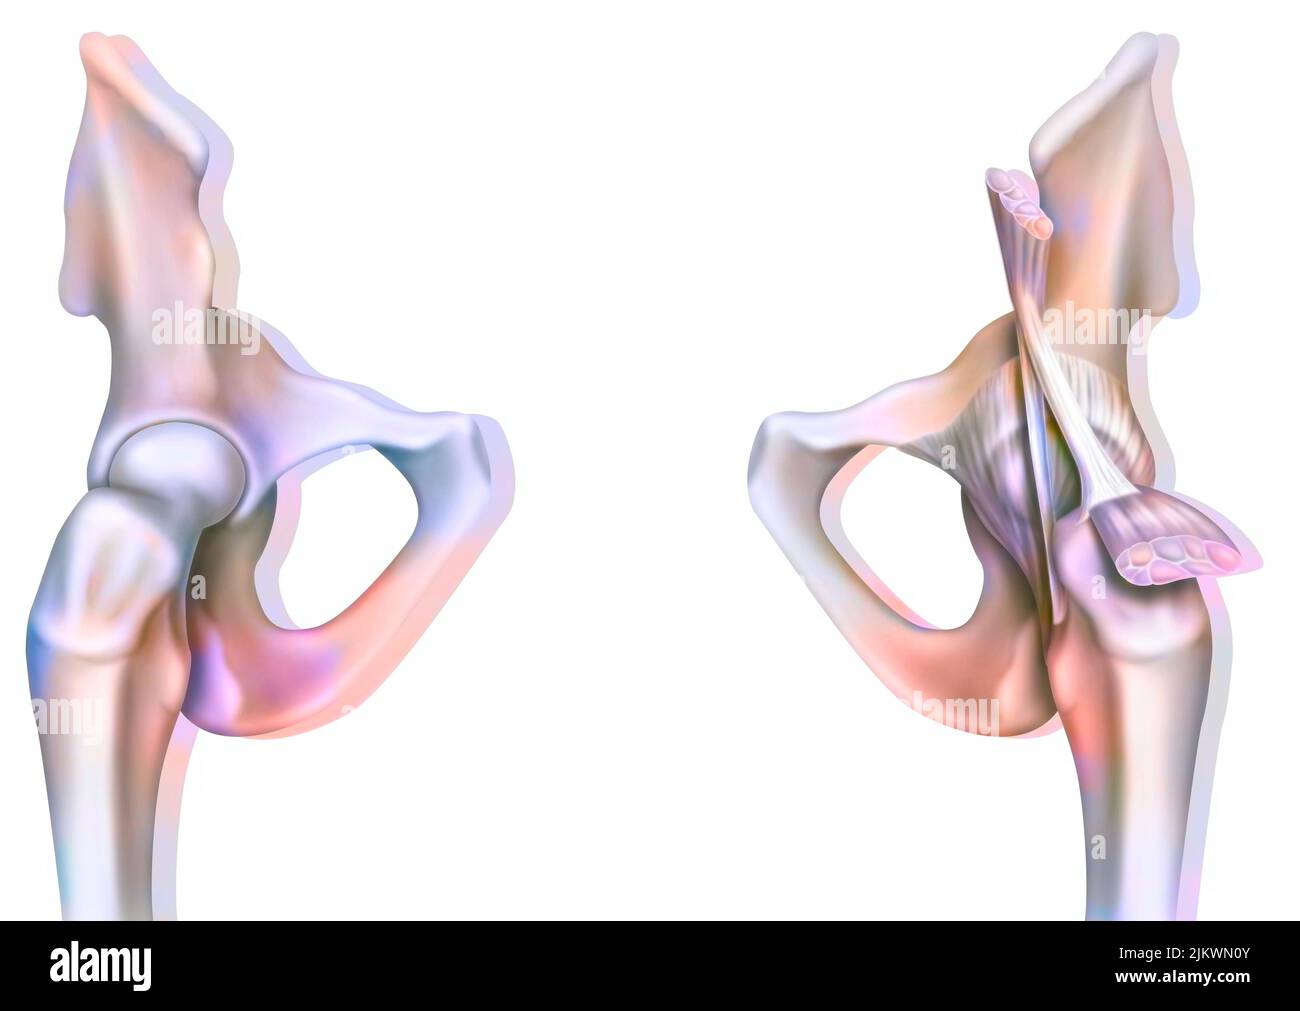

Bone joint of the hip without and with the coxofemoral joint capsule. Stock Photohttps://www.alamy.com/image-license-details/?v=1https://www.alamy.com/bone-joint-of-the-hip-without-and-with-the-coxofemoral-joint-capsule-image476923594.html

Bone joint of the hip without and with the coxofemoral joint capsule. Stock Photohttps://www.alamy.com/image-license-details/?v=1https://www.alamy.com/bone-joint-of-the-hip-without-and-with-the-coxofemoral-joint-capsule-image476923594.htmlRF2JKWMWE–Bone joint of the hip without and with the coxofemoral joint capsule.

Bone joint of the hip without and with the coxofemoral joint capsule. Stock Photohttps://www.alamy.com/image-license-details/?v=1https://www.alamy.com/bone-joint-of-the-hip-without-and-with-the-coxofemoral-joint-capsule-image476923691.html

Bone joint of the hip without and with the coxofemoral joint capsule. Stock Photohttps://www.alamy.com/image-license-details/?v=1https://www.alamy.com/bone-joint-of-the-hip-without-and-with-the-coxofemoral-joint-capsule-image476923691.htmlRF2JKWN0Y–Bone joint of the hip without and with the coxofemoral joint capsule.